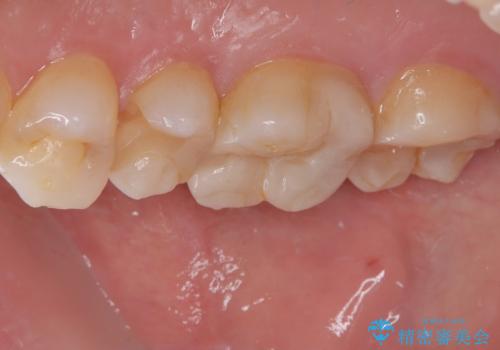

今回のように、奥歯の詰め物の欠けはご自身では気づきにくいケースも多くあります。違和感がなくても、内部で虫歯が進行していることも少なくありません。

そのため、定期的な歯科医院でのチェックとメンテナンスがとても重要です。早期に発見できれば、歯を削る量を最小限に抑えた治療が可能になります。